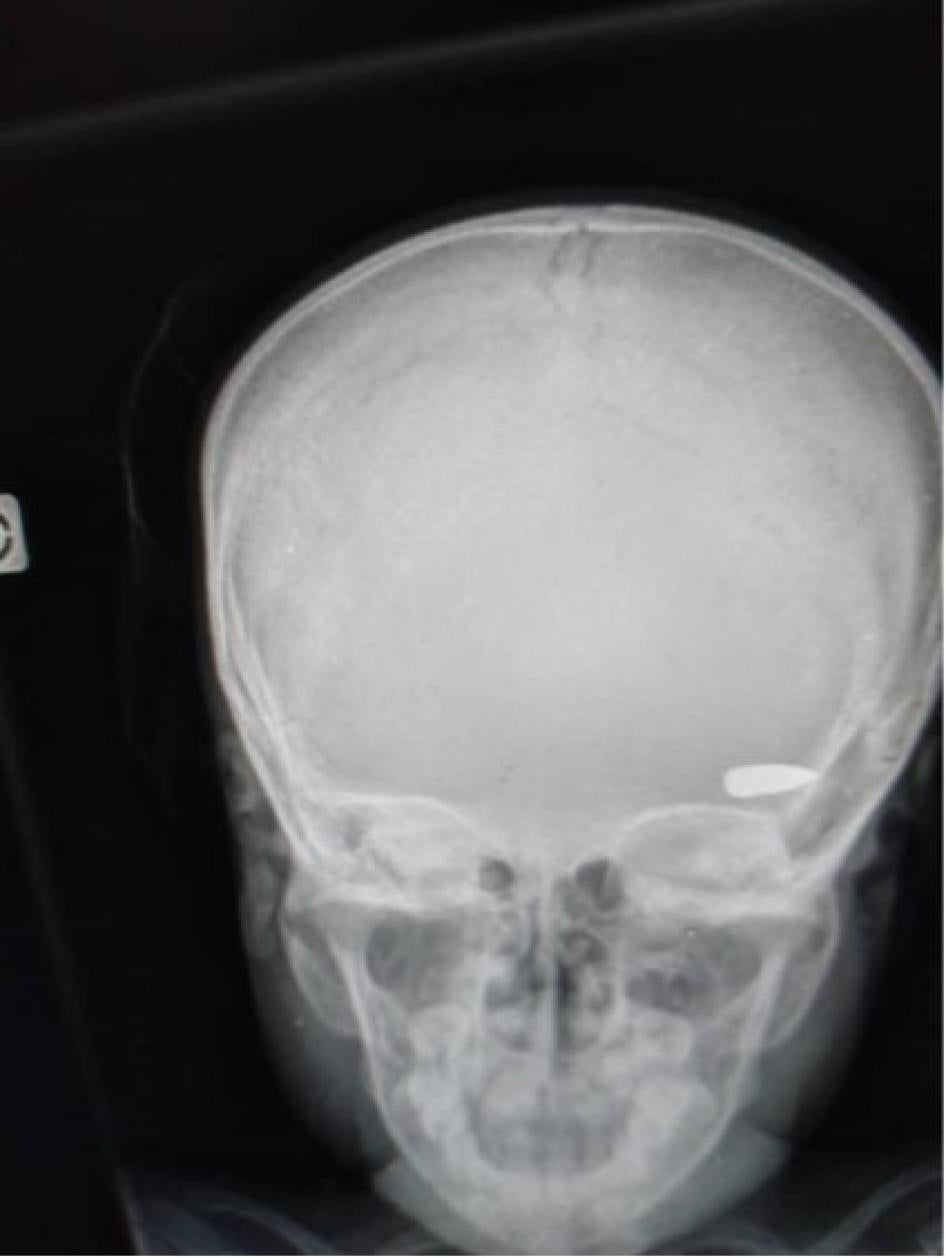

An x-ray image shows a bullet lodged in the head of a child who was hit during a confrontation between criminal groups in the Brooklyn neighborhood of Cité Soleil commune in early April 2023 © 2023 Private